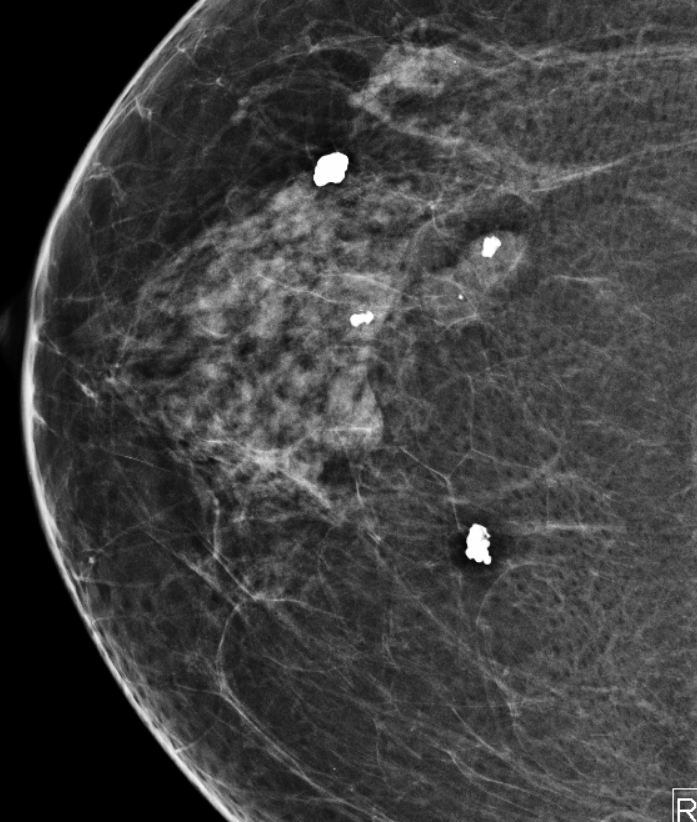

Q

classificação em pipoca, birads 2